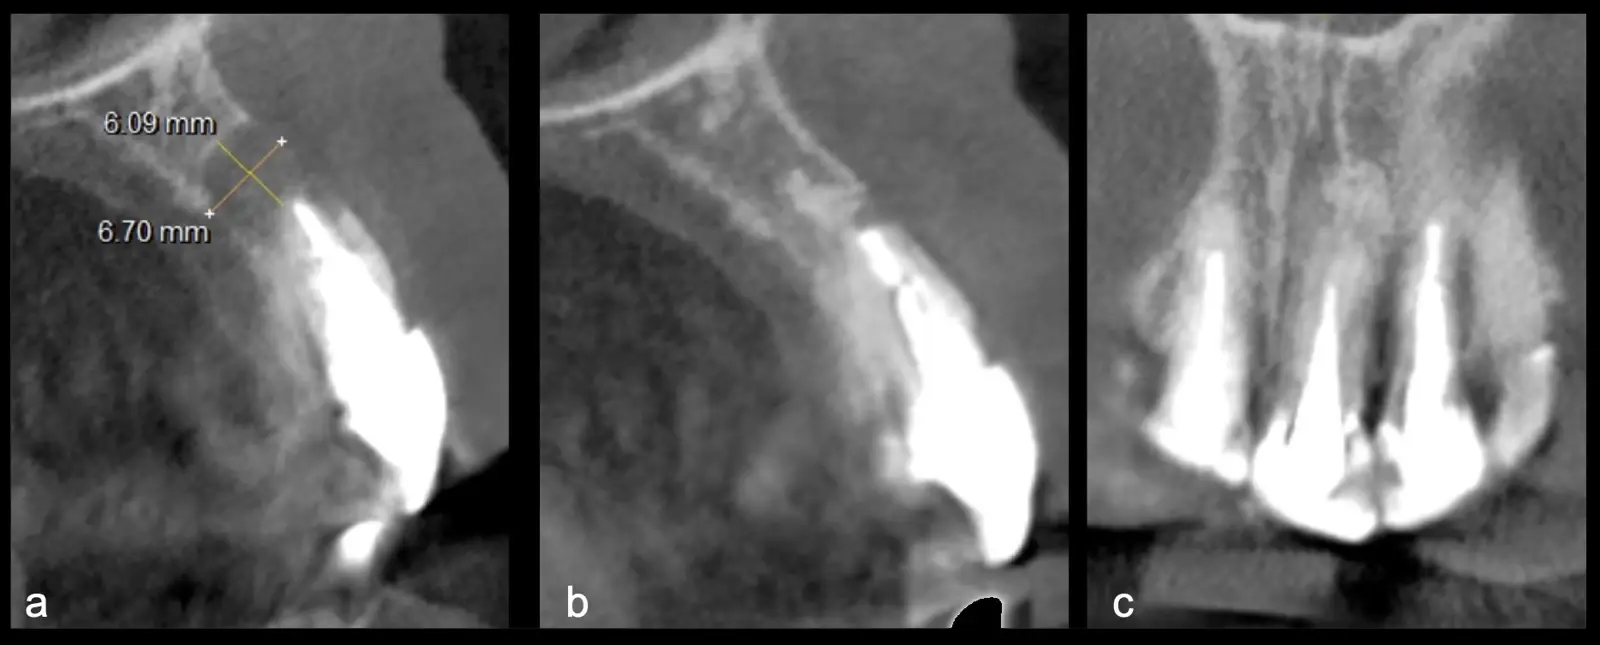

La microcirugía endodóntica apical busca conservar la mayor cantidad de longitud de raíz y de hueso circundante sano para no afectar la estabilidad de la pieza.11 Por ello, es ideal el uso de microscopios, elementos de magnificación, instrumental específico (insertos de ultrasonido endodónticos) y materiales de sellado eficientes para el tratamiento retrogrado. Su éxito es alto y evidencia una cicatrización ósea completa en el 74% de los casos al año de tratamiento.12 Cabe destacar que este logro está asociado también, a predictores propios de cada paciente, como la edad, tipo de pieza, profundidad de sondaje y extensión de la lesión.1 El uso complementario de la tomografía computarizada es resaltante como el instrumento imagenológico de elección para la etapa de planificación microquirúrgica,13 ya sea para una ejecución a mano alzada o con guías prefabricadas.14,15

El procedimiento se inicia colocando anestesia y elevando un colgajo mucoperióstico a espesor completo3 (incisión semilunar o intrasurcular con/sin protección papilar) y exponiendo la zona. En seguida se realiza la enucleación de la lesión, eliminando16 o creando una ventana17 en la lámina cortical que contiene el área del ápice; este retiro óseo se realiza con los insertos de forma aplanada dentada o inserto con cobertura diamantada plano o redondo, recordando ser lo más conservador posible (Figura 5).

Después de realizado el acceso e identificado el ápice, se procede a la limpieza de la zona con instrumentos manuales y/o con insertos diamantados de parte activa angulada para poder eliminar todo el tejido patológico del perímetro radicular apical y del tejido óseo circundante (Figura 6).

Una vez limpia la zona apical, se corrobora la integridad de la raíz y se evalúa el grado de extensión de la lesión. Si el defecto óseo es pequeño, se procede a realizar la preparación del conducto y obturación retrógrada de ser el caso. Si el defecto óseo es de gran tamaño e inaccesible a los insertos, se procede a realizar un corte de por lo menos 3 mm de ápice radicular conteniendo los posibles conductos aún infectados11 empleando habitualmente insertos de borde aserrado con/sin marcas de medición para un trabajo seguro7 (Figura 7).